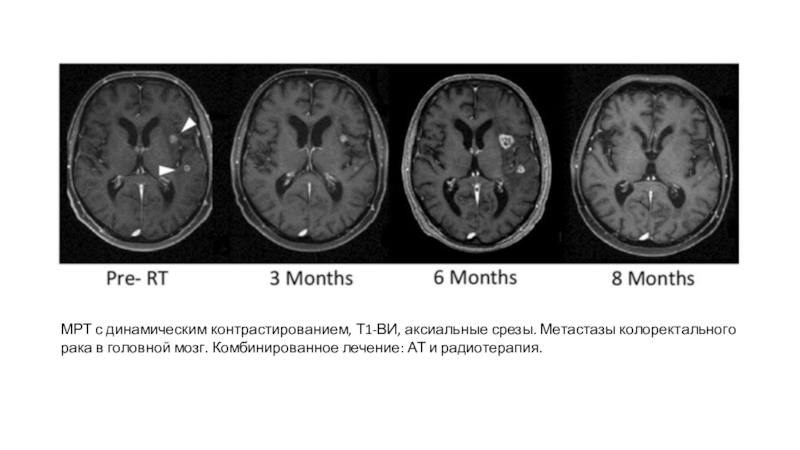

Слайд 43МРТ с динамическим контрастированием, Т1-ВИ, аксиальные срезы. Метастазы колоректального рака

в головной мозг. Комбинированное лечение: АТ и радиотерапия.

МРТ с динамическим контрастированием, Т1-ВИ, аксиальные срезы. Метастазы колоректального рака в головной мозг. Комбинированное лечение: АТ и